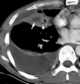

Mucoid impaction in bronchus